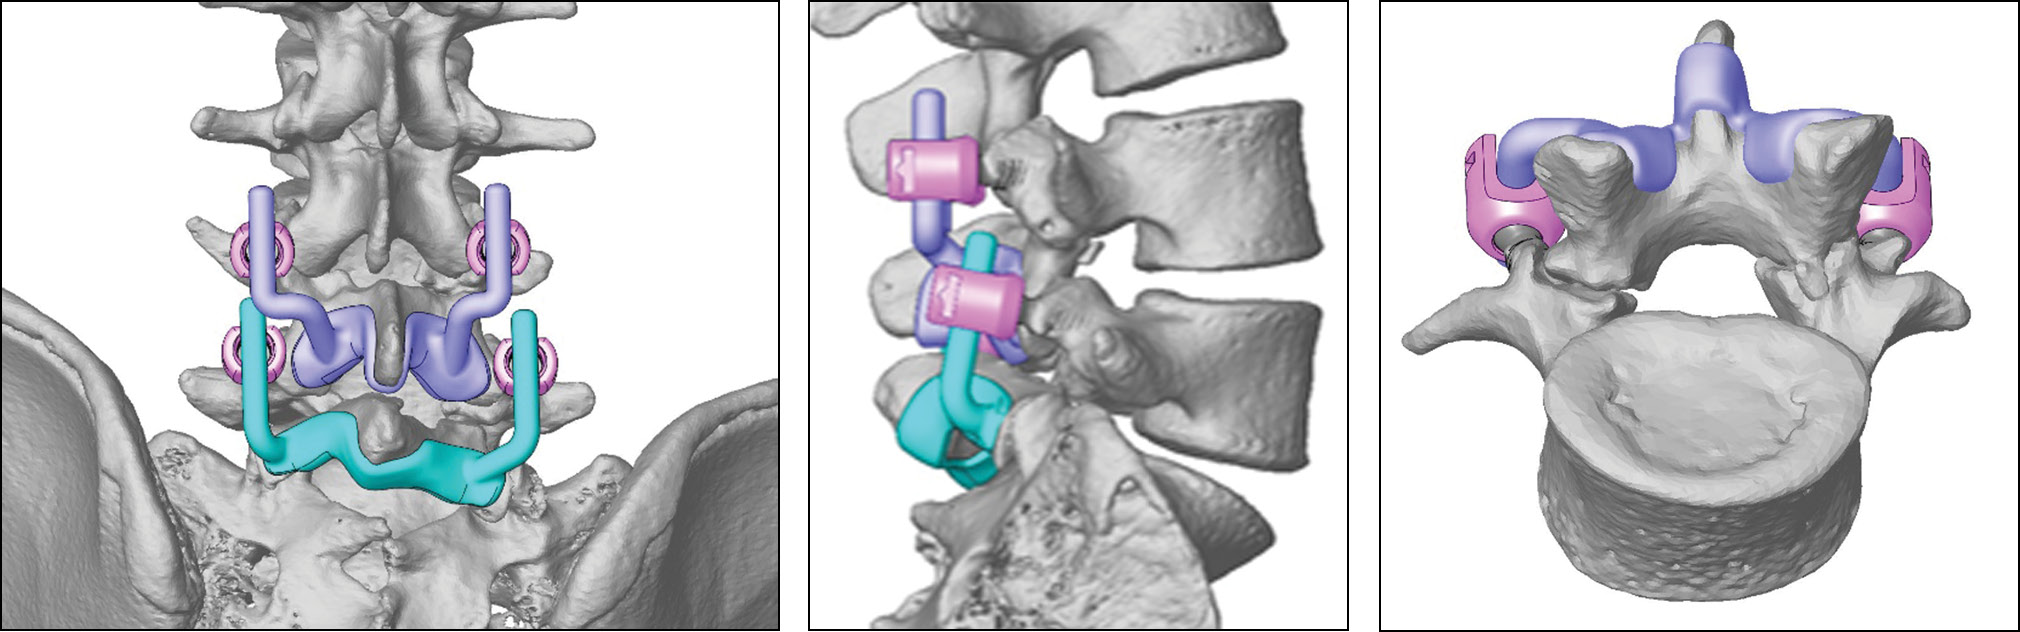

На основании данных КТ совместно с инженерами ООО «Конмет» выполнена компьютерная 3D-реконструкция позвоночника на уровне L4-L5-S1. Изготовлена полноразмерная стереолитографическая модель сегментов L4-L5-S1. На основании представленного проекта индивидуальной конструкции совместно с инженерами осуществлено проектирование конструкций для восстановления целостности дужек L4 и L5 позвонков (рис. 4). Индивидуальные фиксирующие изделия представляли собой два фигурных устройства, соответствующих анатомическому рельефу дорсальной поверхности дужек и нижней поверхности остистых отростков L4 и L5 позвонков. Также на каждом из устройств имелось по два крючкообразных выступа для субламинарной фиксации. Боковые части с левой и правой стороны переходили в стержни стандартного диаметра 5,5 мм для фиксации к транспедикулярным винтам. Важной особенностью проектирования было исключение возможного контакта вышележащих и нижележащих элементов металлоконструкций, установленных на уровне L4 и L5 позвонков соответственно, при движениях в поясничном отделе пациента. Для фиксации использованы серийные транспедикулярные винты, осуществлялся лишь индивидуальный подбор длины и диаметра винта на основании КТ пациента. Спроектированная конструкция изготовлена с использованием аддитивных технологий ООО «Конмет» из сплава Ti-6Al-4V ELI (рис. 5).

Рис. 4. Проект индивидуальной конструкции.

Fig. 4. The project of an individual implant.